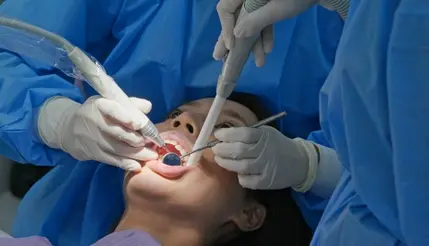

Odontología

"Sonrisas saludables desde la raíz: tu salud bucal es nuestra prioridad."

Centro Odontológico

En nuestro espacio dedicado a la odontología, nos enorgullece ofrecer una amplia gama de servicios diseñados para cuidar su salud bucal de manera integral. Desde procedimientos básicos de mantenimiento hasta tratamientos avanzados, nuestro equipo está aquí para atender todas sus necesidades dentales.

Cirugías Dentales

Incluye una variedad de procedimientos quirúrgicos dentales, como extracciones complejas, cirugía de las encías (periodoncia), colocación de implantes dentales, entre otros.

Tratamientos de Conducto

También conocido como endodoncia, es un procedimiento para tratar infecciones o lesiones en la pulpa dental. Implica la eliminación del tejido infectado, la limpieza y el sellado del conducto radicular para salvar el diente.